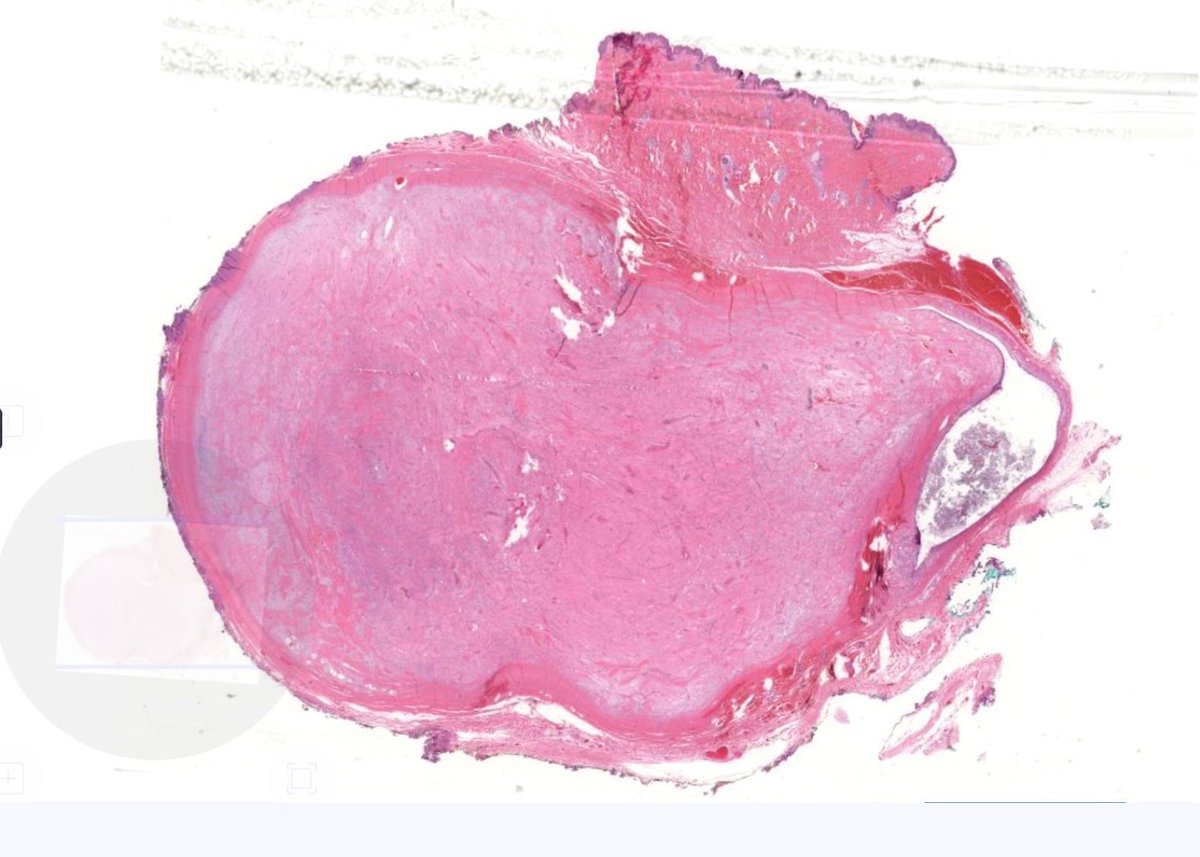

Soft tissue nodule. Can you diagnose it from one pic, or is it #TooLowToDiagnose? Answer ✅ youtu.be/EPyakVOCmFs?si… Digital slide: kikoxp.com/posts/51103 #pathology #pathTwitter #dermpath #dermatology #parasitology #dermatologia #dermtwitter

Soft tissue nodule. Can you diagnose it from one pic, or is it #TooLowToDiagnose?

Answer ✅ youtu.be/EPyakVOCmFs?si…

Digital slide: kikoxp.com/posts/51103

#pathology #pathTwitter #dermpath #dermatology #parasitology #dermatologia #dermtwitter